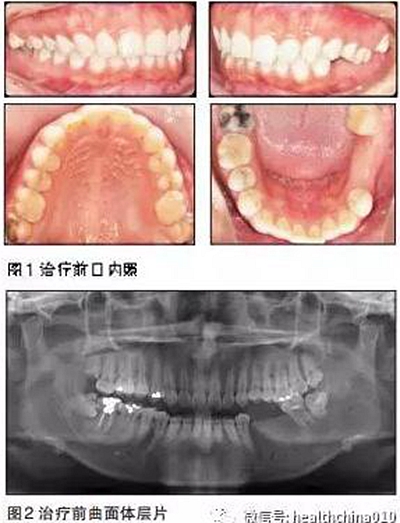

臨床檢查

患者臉型不對(duì)稱,右側(cè)大于左側(cè)。

牙周情況尚可,有少量牙結(jié)石,牙齦無(wú)明顯紅腫。35、36缺失,25、26過(guò)長(zhǎng),17與47,27與37正鎖牙合,咬合時(shí)26、27的牙尖頂?shù)綄?duì)頜缺牙區(qū)牙槽嵴黏膜上。37、47死髓牙。

全口曲面體層片顯示:35、36缺失,缺牙區(qū)牙槽骨有足夠的骨高度,47未行根管治療,38、48近中阻生,18殘根,28頰面深齲近髓。